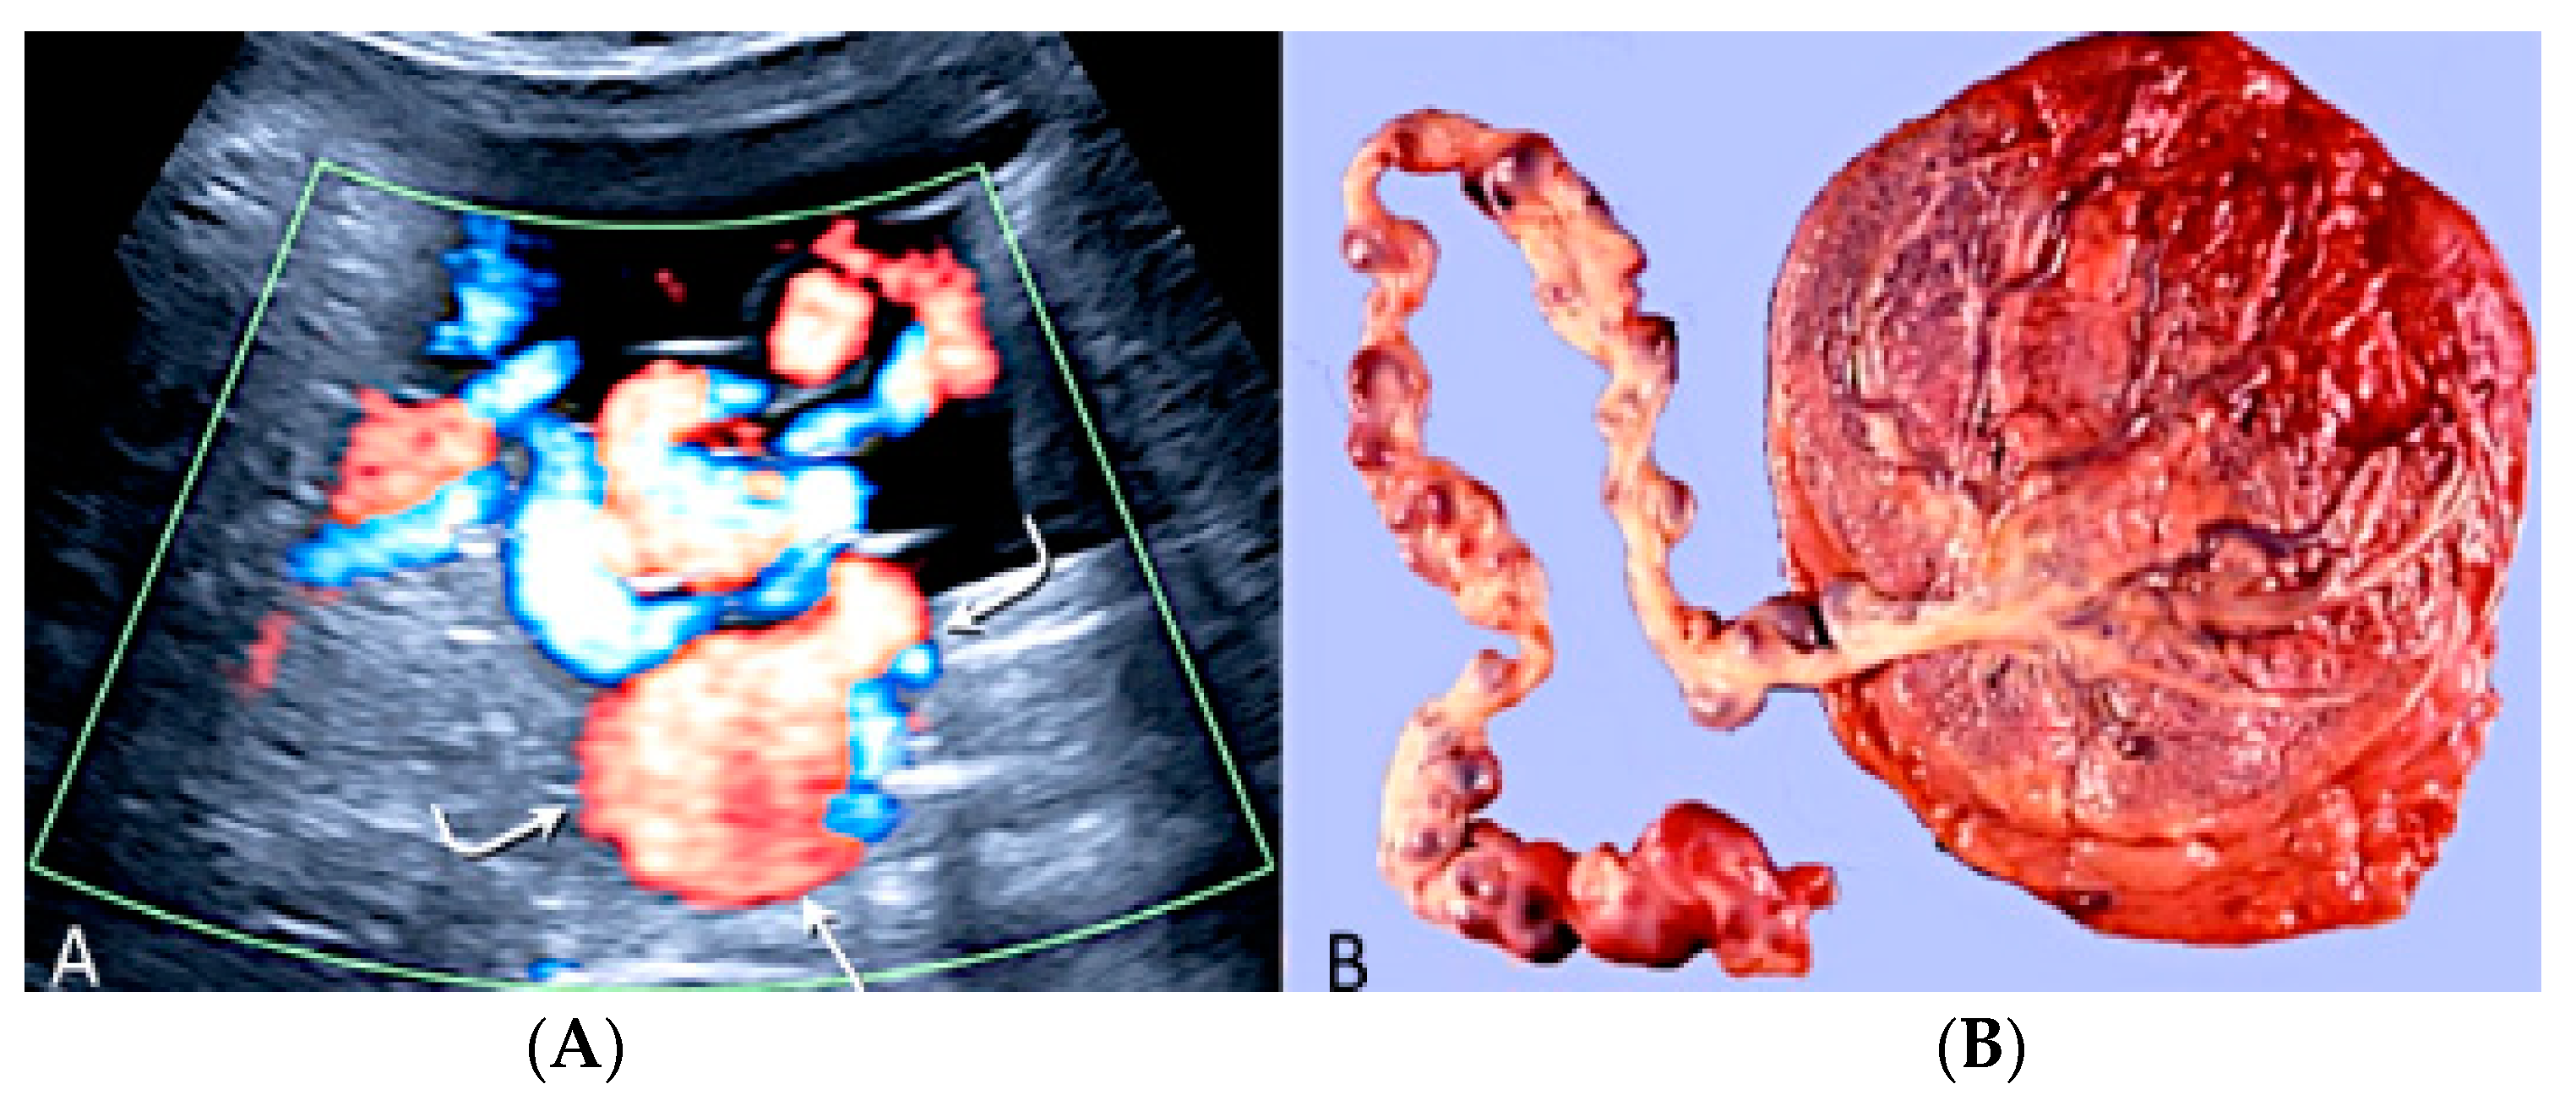

3.2.11. Umbilical Cord Varix

Umbilical cord varix is a rare condition in which there is a focal dilatation larger than 9.0 mm in the intrahepatic or extrahepatic portion of the umbilical vein [47,68]. It is associated with a 5.8% risk of chromosomal aneuploidy, especially trisomy 21, and a 19% risk of additional ultrasound anomalies [68]. At ultrasound examination, a cystic structure is seen in the fetal abdomen, showing differential diagnosis to normal fetal gallbladder and fetal stomach mesenteric or omental cysts and umbilical artery aneurisms [47]. Doppler ultrasound evaluation is essential for a correct diagnosis [47] (Figure 32).

Figure 32.

Doppler ultrasound (A) demonstrating an umbilical cord varix (curved arrows) with pathology confirmation after birth (B).